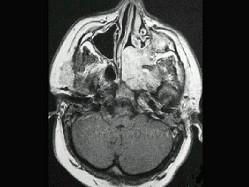

男性,19岁,左侧鼻腔反复出血一年余,CT、MRI扫描如图所示,请选择最可能诊断 ( )

答案: E